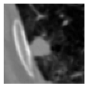

3.4.2. Representative Cases with Segmentation Challenges on the MEF-PN35 Dataset

To complement the quantitative evaluation, we present a set of representative cases from the clinical dataset that exhibited typical segmentation challenges. These cases were selected to reflect diverse morphological characteristics observed in pulmonary nodules, such as spiculated boundaries, small size, vessel adherence, pleural attachment, cavitation, and clear isolation. Rather than aiming for exhaustive categorization, our intent is to highlight a range of practical difficulties encountered in real-world scenarios and to qualitatively assess how different boundary-aware loss functions respond to these variations. Each challenge is labeled (C1) through (C5) in Table 10 and is consistently referenced in the corresponding detailed illustrations that follow.

Following the summary in Table 11, we present detailed visual comparisons for selected representative cases, each corresponding to a specific segmentation challenge. These cases are consistently labeled using the Challenge ID (CID) codes defined in Table 9 to facilitate cross-referencing between the summary and the case illustrations. Each table reports segmentation results across three loss configurations (Sobel, Laplacian, and Hausdorff) using five columns. Loss indicates the boundary loss formulation applied in each case, where Dice loss is combined with a boundary term computed using Sobel, Laplacian, or Hausdorff operators. The Segmentation Result column shows four images side by side: the input CT patch, the manual ground truth, the model prediction, and a color-coded difference map between ground truth and prediction. In this map, green indicates true positives, blue represents true negatives, red corresponds to false positives, and yellow denotes false negatives. The final column, Attention Map, presents Grad-CAM visualizations derived from one of the Adaptive Attention Fusion (AAF) layers in the encoder path. These maps illustrate the spatial focus of the model, with red/yellow regions indicating strong attention and lighter or neutral tones indicating lower activation. All six cases are presented in detail in Table 11, Table 12 and Table 13, providing a comprehensive qualitative analysis of how each loss configuration performs under specific segmentation challenges observed in real clinical data.